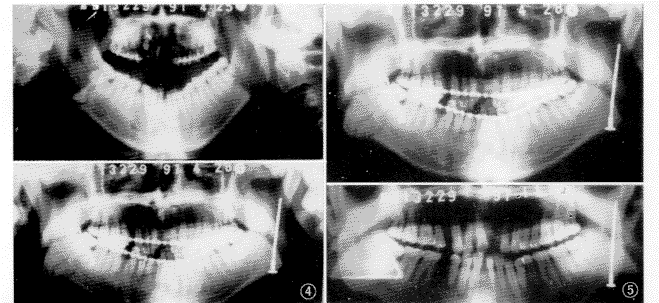

移位性髁突骨折的治疗有意义,临床效果好,避免了髁突移位性骨折常见的并发症。同时,该技术避免了长期颌间结扎,6例术后均未行颌间结扎,其中3例伴上颌或下颌的牙槽突骨折,行单颌牙弓夹板固定(图4,5)。传统的颌间结扎的方法对伴牙槽突骨折的固定常常不利。

3.复位技术:本组的6例髁突骨折均系对冲伤所致,其中5例除髁突骨折外,还伴有下颌骨正中或下颌体部骨折,1例仅出现髁突骨折。若伴其他骨折时,作者均先行下颌其他部位骨折复位固定,最后行髁突轴向拉力螺钉固定术,以保证恢复咬合关系(图4,5)。具体方法:首先利用暂时性颌间结扎恢复咬合关系,口内相应部位切口入路暴露下颌体部骨折线,小型钛板坚固内固定,冲洗缝合后,打开临时性颌间结扎,换橡皮筋弹力牵引。然后,口外下颌角皮肤切口入路,沿下颌升支外侧面暴露髁突骨折线,然后再向上细心寻找移位的髁突骨断端,本研究中,凡骨折断端移位于下颌升支内侧者,其暴露及复位的难度较大,但完全可以复位(图7)。首先从下颌角处向下牵拉下颌骨,使下颌升支在骨折线处有一定空间,用专用骨钳寻找,夹持髁突骨断端并使其复位,再解除下颌角部位的牵拉,此时口内有临时性橡皮筋弹力牵引,检查咬合关系后再次检查髁突骨段复位情况,然后直视下先在骨折线升支侧靠近升支后缘用球钻去除颊侧骨皮质形成一窗口(图2),然后经下颌角钻一升支内隧道,再用专用钻头经隧道在髁突骨段的骨折断面上为拉力螺钉备洞,术者可经骨折线下颌升支一侧的窗口直视并调整拉力螺钉备洞的角度与位置,以保证拉力螺钉理想的固定位置。我们体会,该技术成功的关键是移位髁突骨段尽可能的准确复位,因骨折部位深、视野小、手术切口受一定解剖结构限制,在三维方向上精确复位移动髁突骨断端有一定难度,但手术技巧很主要。首先,在骨块复位尚未固定时检查咬合关系;直视骨折线两侧骨块是否紧密接触,骨折线是否密合;直视检查髁突骨断端后缘是否与下颌升支后缘平滑移行;此时,按步骤行轴向拉力螺钉固定。固定完毕后,立即去除颌间弹力牵引,使下颌被动运动以检查咬合关系。本组6例髁突骨折均系移位性骨折,术后X线复查,在曲面体层片上,4例髁突长轴与下颌升支后缘长轴未能完全一致,1例髁突在术后X线后前位片上仍略向内倾斜(表4),临床检查6例咬合关系均良好,无张口受限,无关节区不适。说明,通过下颌角入路,在三维方向上完全恢复髁突术前解剖生理位置有一定难度,但髁突骨折轴向拉力螺钉技术对于复位固定髁突骨折、恢复髁突的生理功能、防止相应并发症是行之有效的(图6~9)。